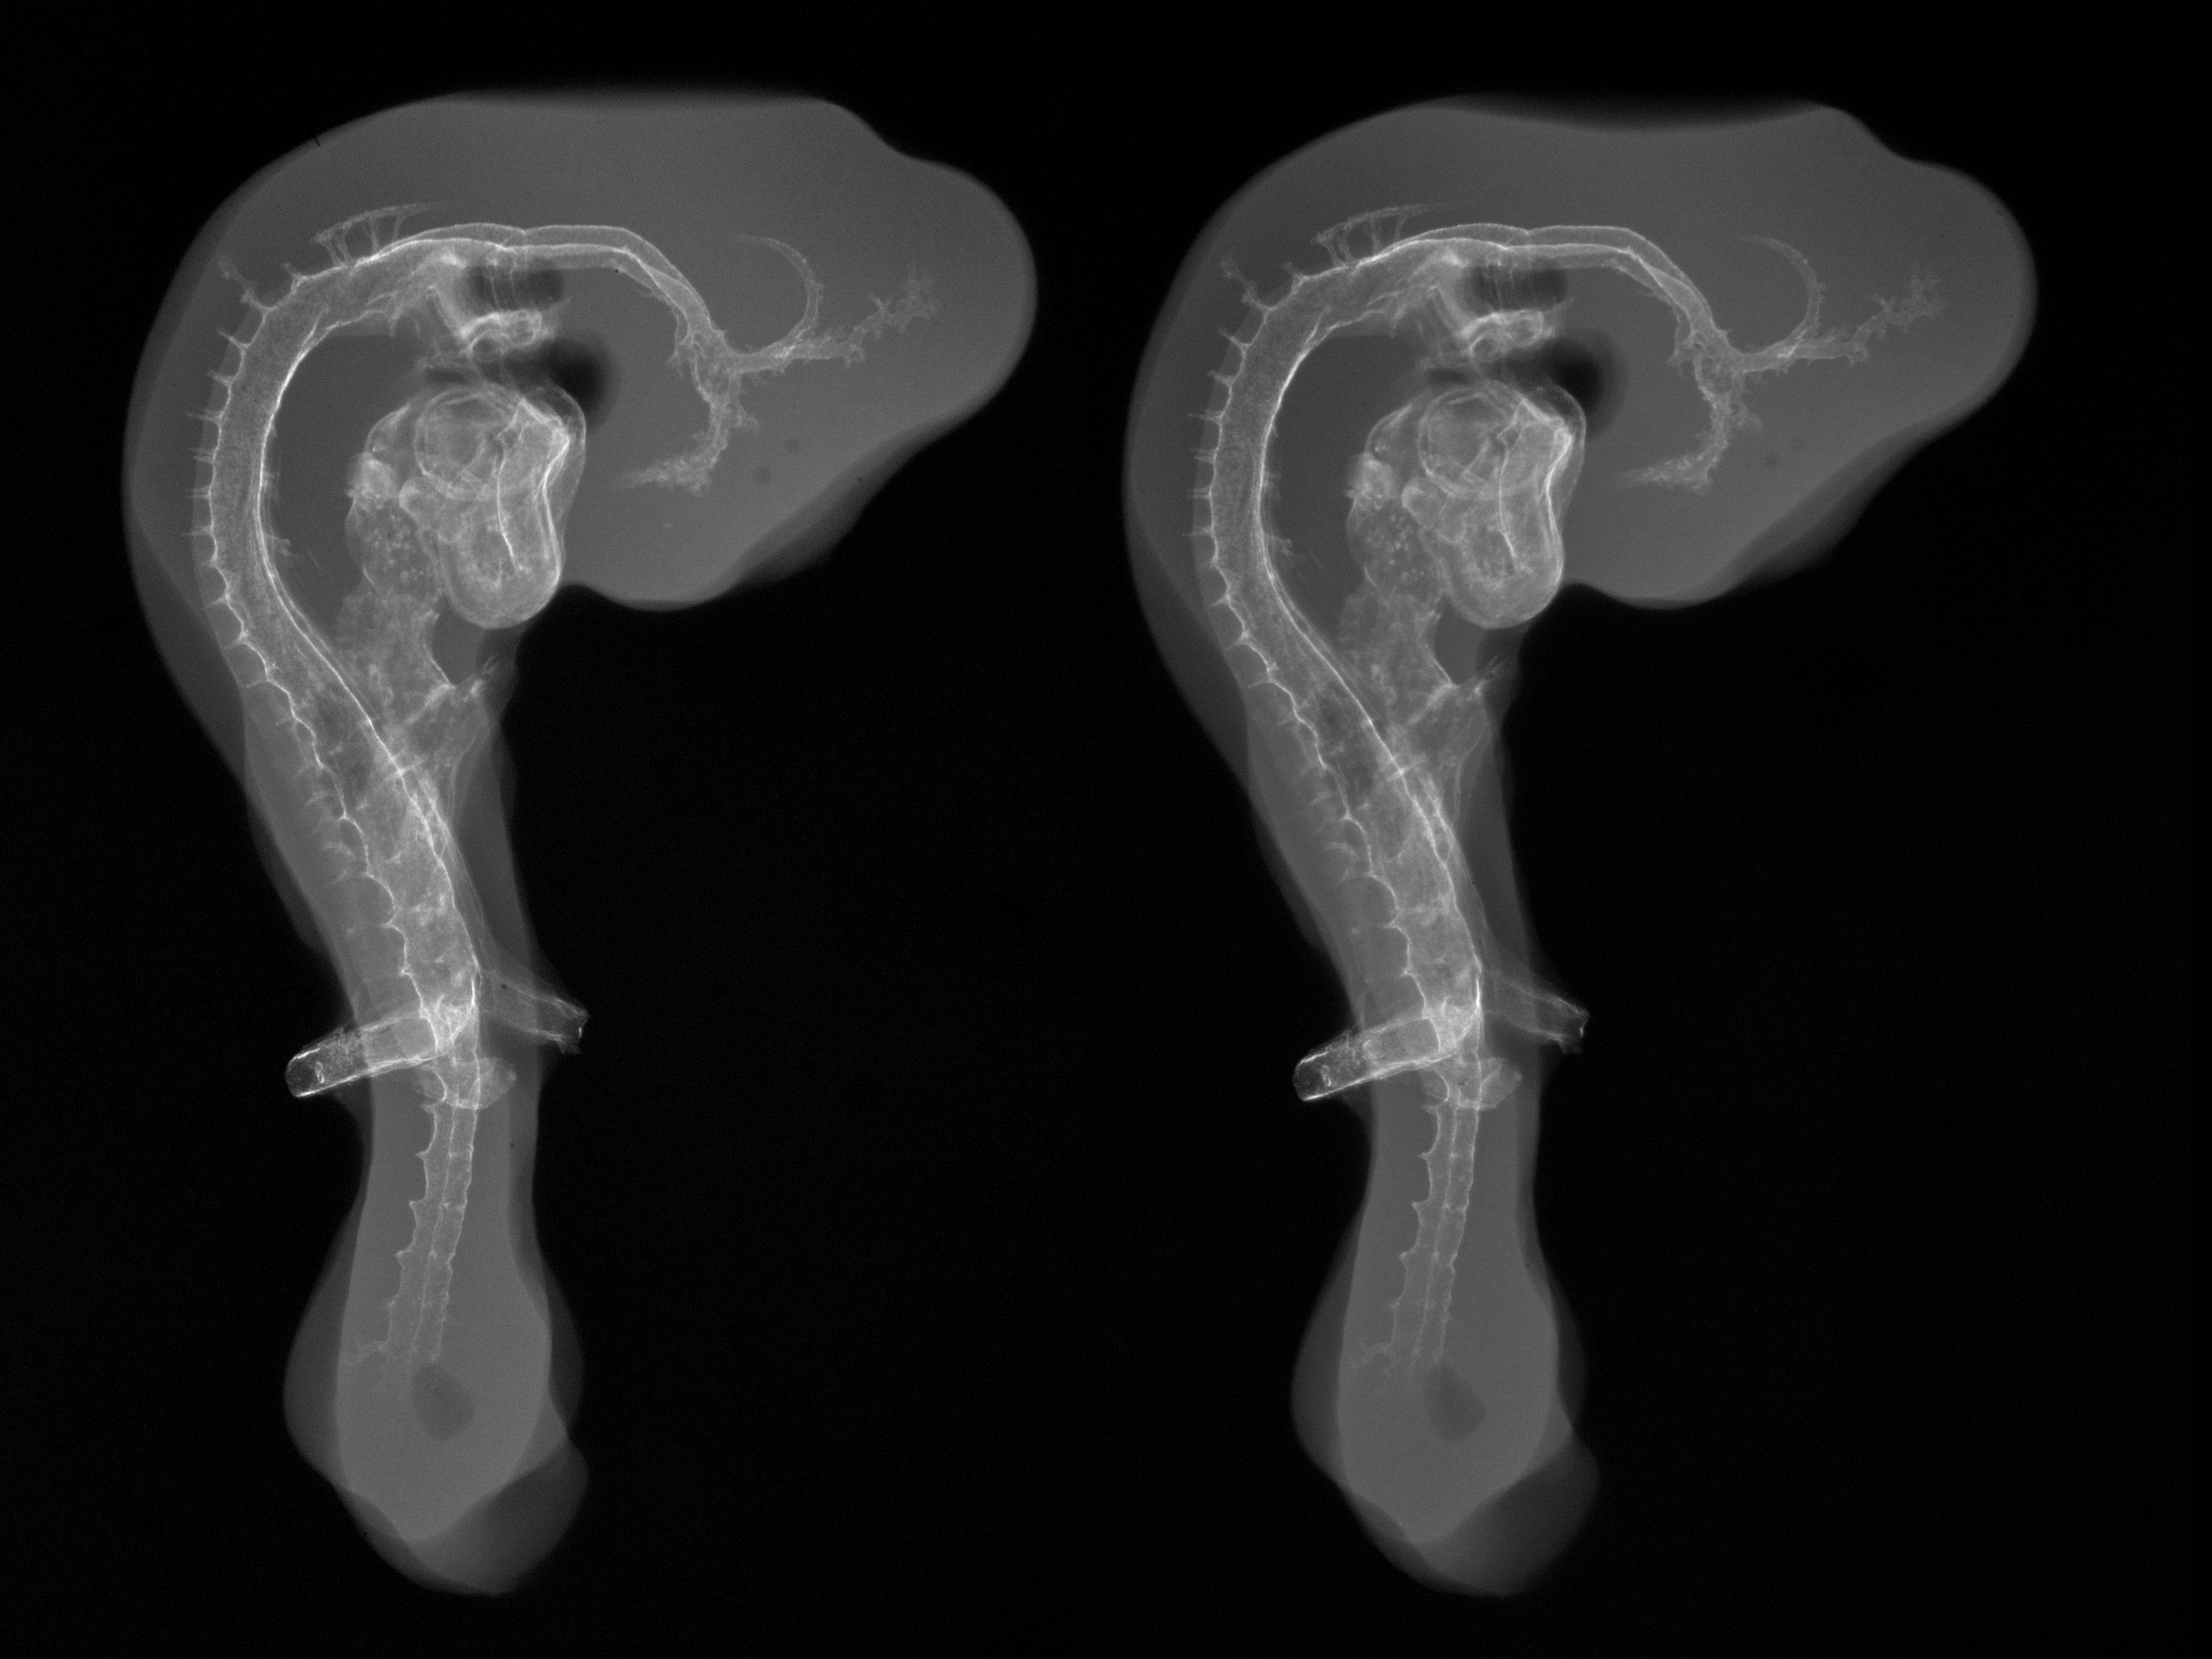

Chick Embryo Microangiography

Hamburger-Hamilton (HH) Stage 19 (approx. 3 - 3.5 days)

Stereo X-Ray Micrographs